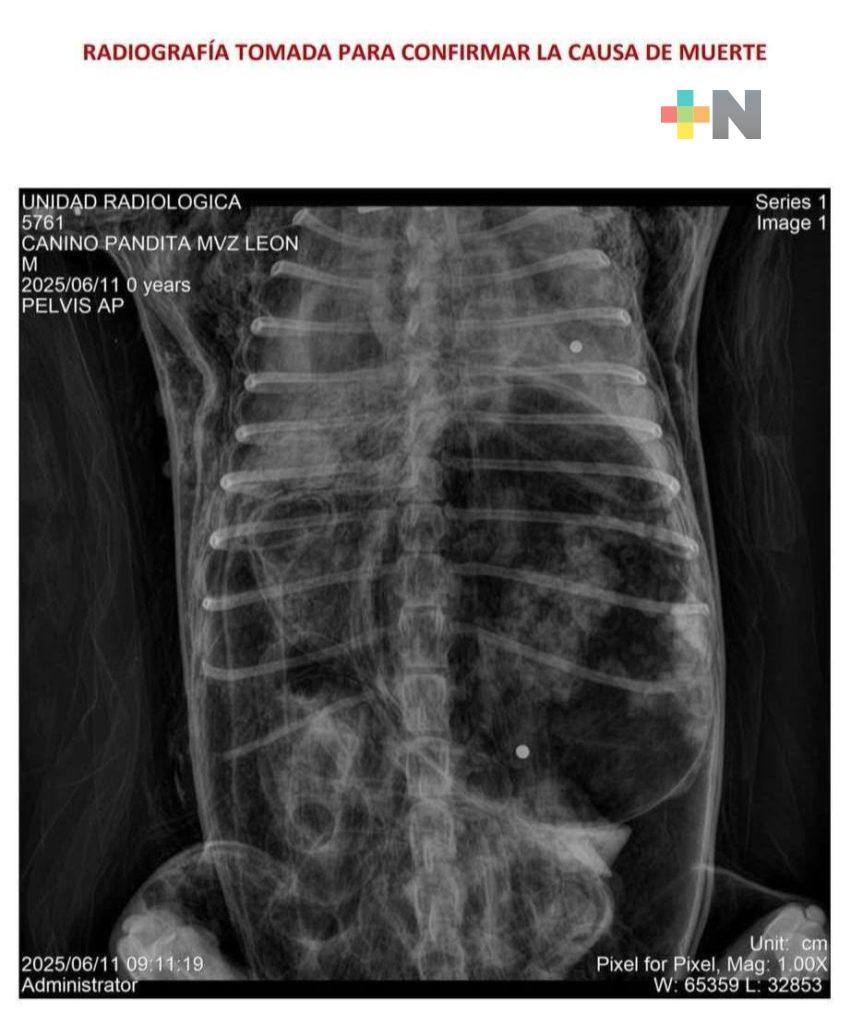

De acuerdo con la familia afectada, el ataque se registró mientras Pandita se encontraba en el patio, recién bañado, a punto de ser llevado al frente de la vivienda, donde solía pasar gran parte del día. En cuestión de segundos, el can recibió dos impactos de balines tipo diábolo que le arrebataron la vida de manera instantánea.